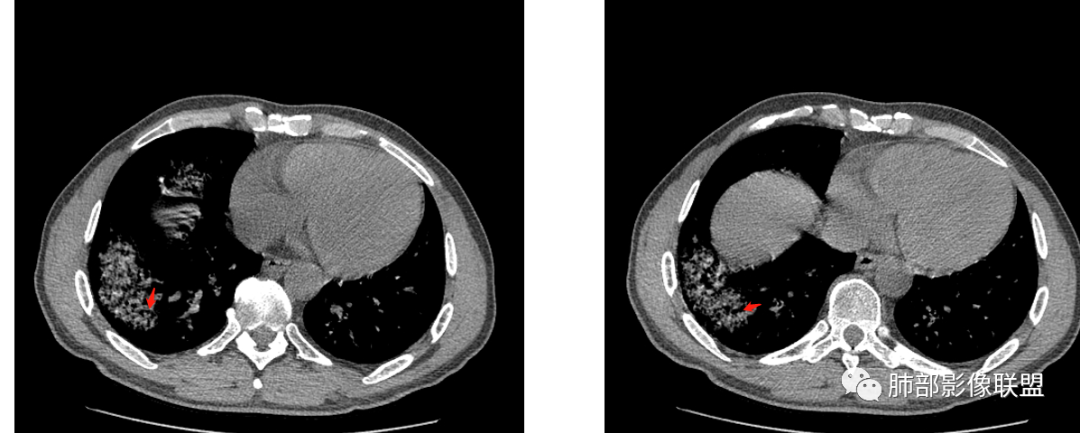

患者,男,49岁,初次以头晕呕吐肾功能异常入院,后期伴双下肢水肿,CT示双肺多发斑片及结节影,部分周围伴晕,部分内部可见支气管穿行,多次复查可见部分病灶略吸收及新发病灶出现,最后一次复查双肺多发磨玻璃样改变,综合考虑血管炎,最后一次伴肺水肿可能

中年男性,高血压,肾功能衰竭,贫血病史,尿潜血阳性。3.8双肺野多发斑片磨玻璃实变影,结节影,边缘模糊,周围有晕征,内见支气管充气征,主要沿支气管血管束分布,部分胸膜下分布,3.12号病灶有吸收好转,4.8号斑片实变影基本吸收,主要沿支气管血管束分布结节影,边缘平直收缩,4.28病灶大部分吸收好转,双肺支气管血管束增粗,有少量结节影。考虑ANCA相关性血管炎可能性大,第一次片子觉得隐球菌不排除,但是后面没有抗真菌治疗就吸收了,觉得隐球菌可能性不大。

影像:双肺散在实变影及毛玻璃影,实性病变周围可见晕征,病灶于肺外围区域优势分布,病变区引流支气管未见增厚,考虑血管相关病变;3月、4月复查CT提示肺内病灶呈游走性,此起彼伏。

胸部CT:双肺多发实性斑片影,散在GGO。实性斑片周围可见晕征、边缘模糊不清,病灶于肺外围区域优势分布。肺门区血管影增粗,支气管套袖,目测肺动脉增粗。3月、4月复查肺内实性斑片病灶呈游走性,此起彼伏。

双肺多发斑片及结节状磨玻璃影,部分内部可见支气管穿行,多次复查可见部分病灶略吸收及新发病灶出现,肾功能不全,贫血,综合考虑肺泡出血,血管炎。

谢加平:

双肺多发斑片影,沿支气管血束分布,前后复查对比,大部分有吸收好转,另外新发(此起彼伏特点),患者肾功能不全及肾性高血压,首选血管炎,并肺泡出血可能。